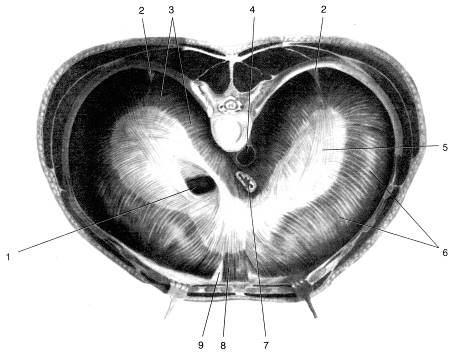

Анатомия диафрагмы и треугольника Бохдалека